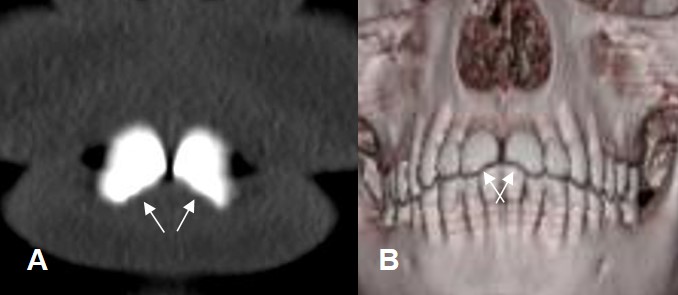

Fig 74 B. Fractura dental.

A: TAC reconstrucción coronal y B: TAC reconstrucción 3D. Fractura en la parte

infero-medial de ambos incisivos.